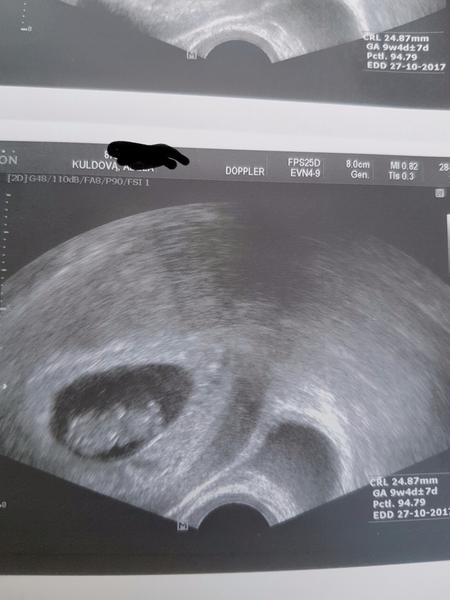

Blahopřeji, mám radost 🙂. My jsme na tom s fazolkou také dobře. Druhý utz. mám přesně za týden a poprvé už u gyn.lékařky. V CAR už jsme skončili. Jinak jsme o týden mladší než "Adusku" 🙂. A co ostatní holčiny, jak to s vámi vypadá, jak se cítíte?

@adusku a ja az 25.4. dnes jsem 10+1 🙂